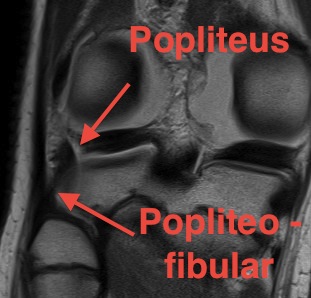

Popliteus anatomy

Don't see entire length on single images

- coronal image to see insertion onto popliteal fossa below LCL

- follow tendon around on coronal images

- watch as becomes musculo-tendinous (can often be torn here)

- muscle inserts onto posteromedial tibia

Normal anatomy

Popliteofibular ligament anatomy

Normal anatomy

Injury